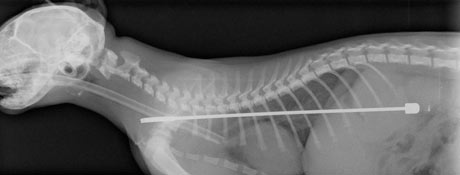

Σε έκτακτη χειρουργική επέμβαση υπεβλήθη νεαρός γάτος ονόματι Άλφι, η μανία του οποίου

με την τηλεόραση τον έκανε να φάει την μήκους 15 εκατοστών κεραία της.

Αμετανόητος πολέμιος του απεχθούς μέσου μαζικής ενημέρωσης, το τετράποδο αιλουροειδές αποφάσισε να βάλει μια για πάντα τέλος στο «χαζοκούτι», ρίχοντάς το κάτω και «μασουλώντας» τη μεταλλική κεραία, η οποία ευτυχώς δεν του τραυμάτισε τη στομαχική κοιλότητα.